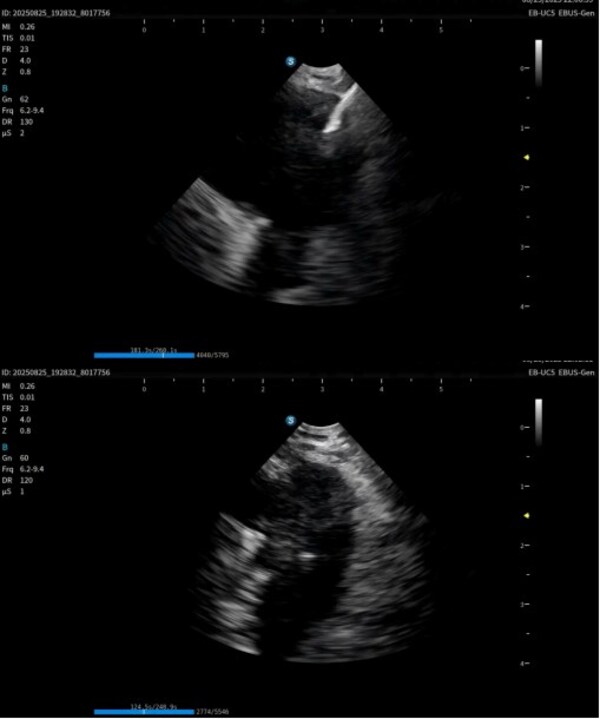

作為在呼吸診療領(lǐng)域的重磅產(chǎn)品,本次在產(chǎn)品創(chuàng)新設(shè)計(jì)上和工藝技術(shù)上取得了重大突破,顯著提升了光學(xué)圖像和超聲圖像的質(zhì)量,同時(shí)鏡體保持了良好的操作性,在鉗鏡比和視野角綜合參數(shù)可達(dá)到全球同類產(chǎn)品最佳性能。目前在臨床應(yīng)用表現(xiàn)突出,取得了專家的認(rèn)可和好評(píng)。

超聲電子支氣管內(nèi)窺鏡憑借其"微創(chuàng)、精準(zhǔn)、安全"的特點(diǎn),已成為呼吸介入領(lǐng)域的核心技術(shù)之一。開(kāi)立醫(yī)療全系列產(chǎn)品全面上市可為肺部腫瘤、縱隔病變提供管內(nèi)清晰光學(xué)影像,管外高清聲學(xué)斷層組織及血流影像,提供精準(zhǔn)可視化介入操作,為疾病的診斷提供更精準(zhǔn)、更安全、更高效的一體化診療解決方案。